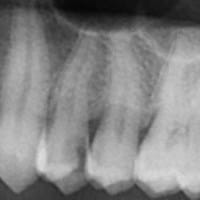

Busco el consejo de un especialista que me confirme la indicación de endodoncia en vista de la prueba que aporto